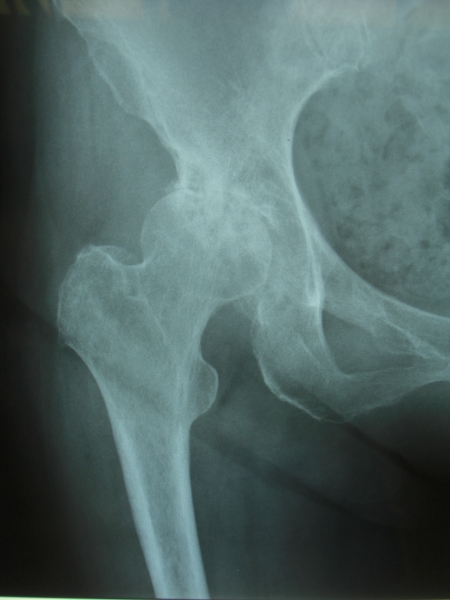

変形性股関節症のレントゲン像(A)と骨頭表面(B)および断面(C)、THA術後(D)

変形性股関節症

股関節疾患の中では最も重要で一次性と二次性に分けられていますが、本邦では先天性股関節脱臼に関係する二次性変形性股関節症が殆どです。

本疾患は前期、初期、進行期、末期の4段階に分類され、先天性股関節脱臼治療後の遺残臼蓋形成不全あるいは未治療の臼蓋形成不全

(X線のみで診断、本人は気付かないことが殆ど)が成長終了後あたりから徐々に進行していきます。患者さんはまず股関節の痛みで整形外科を受診されます。